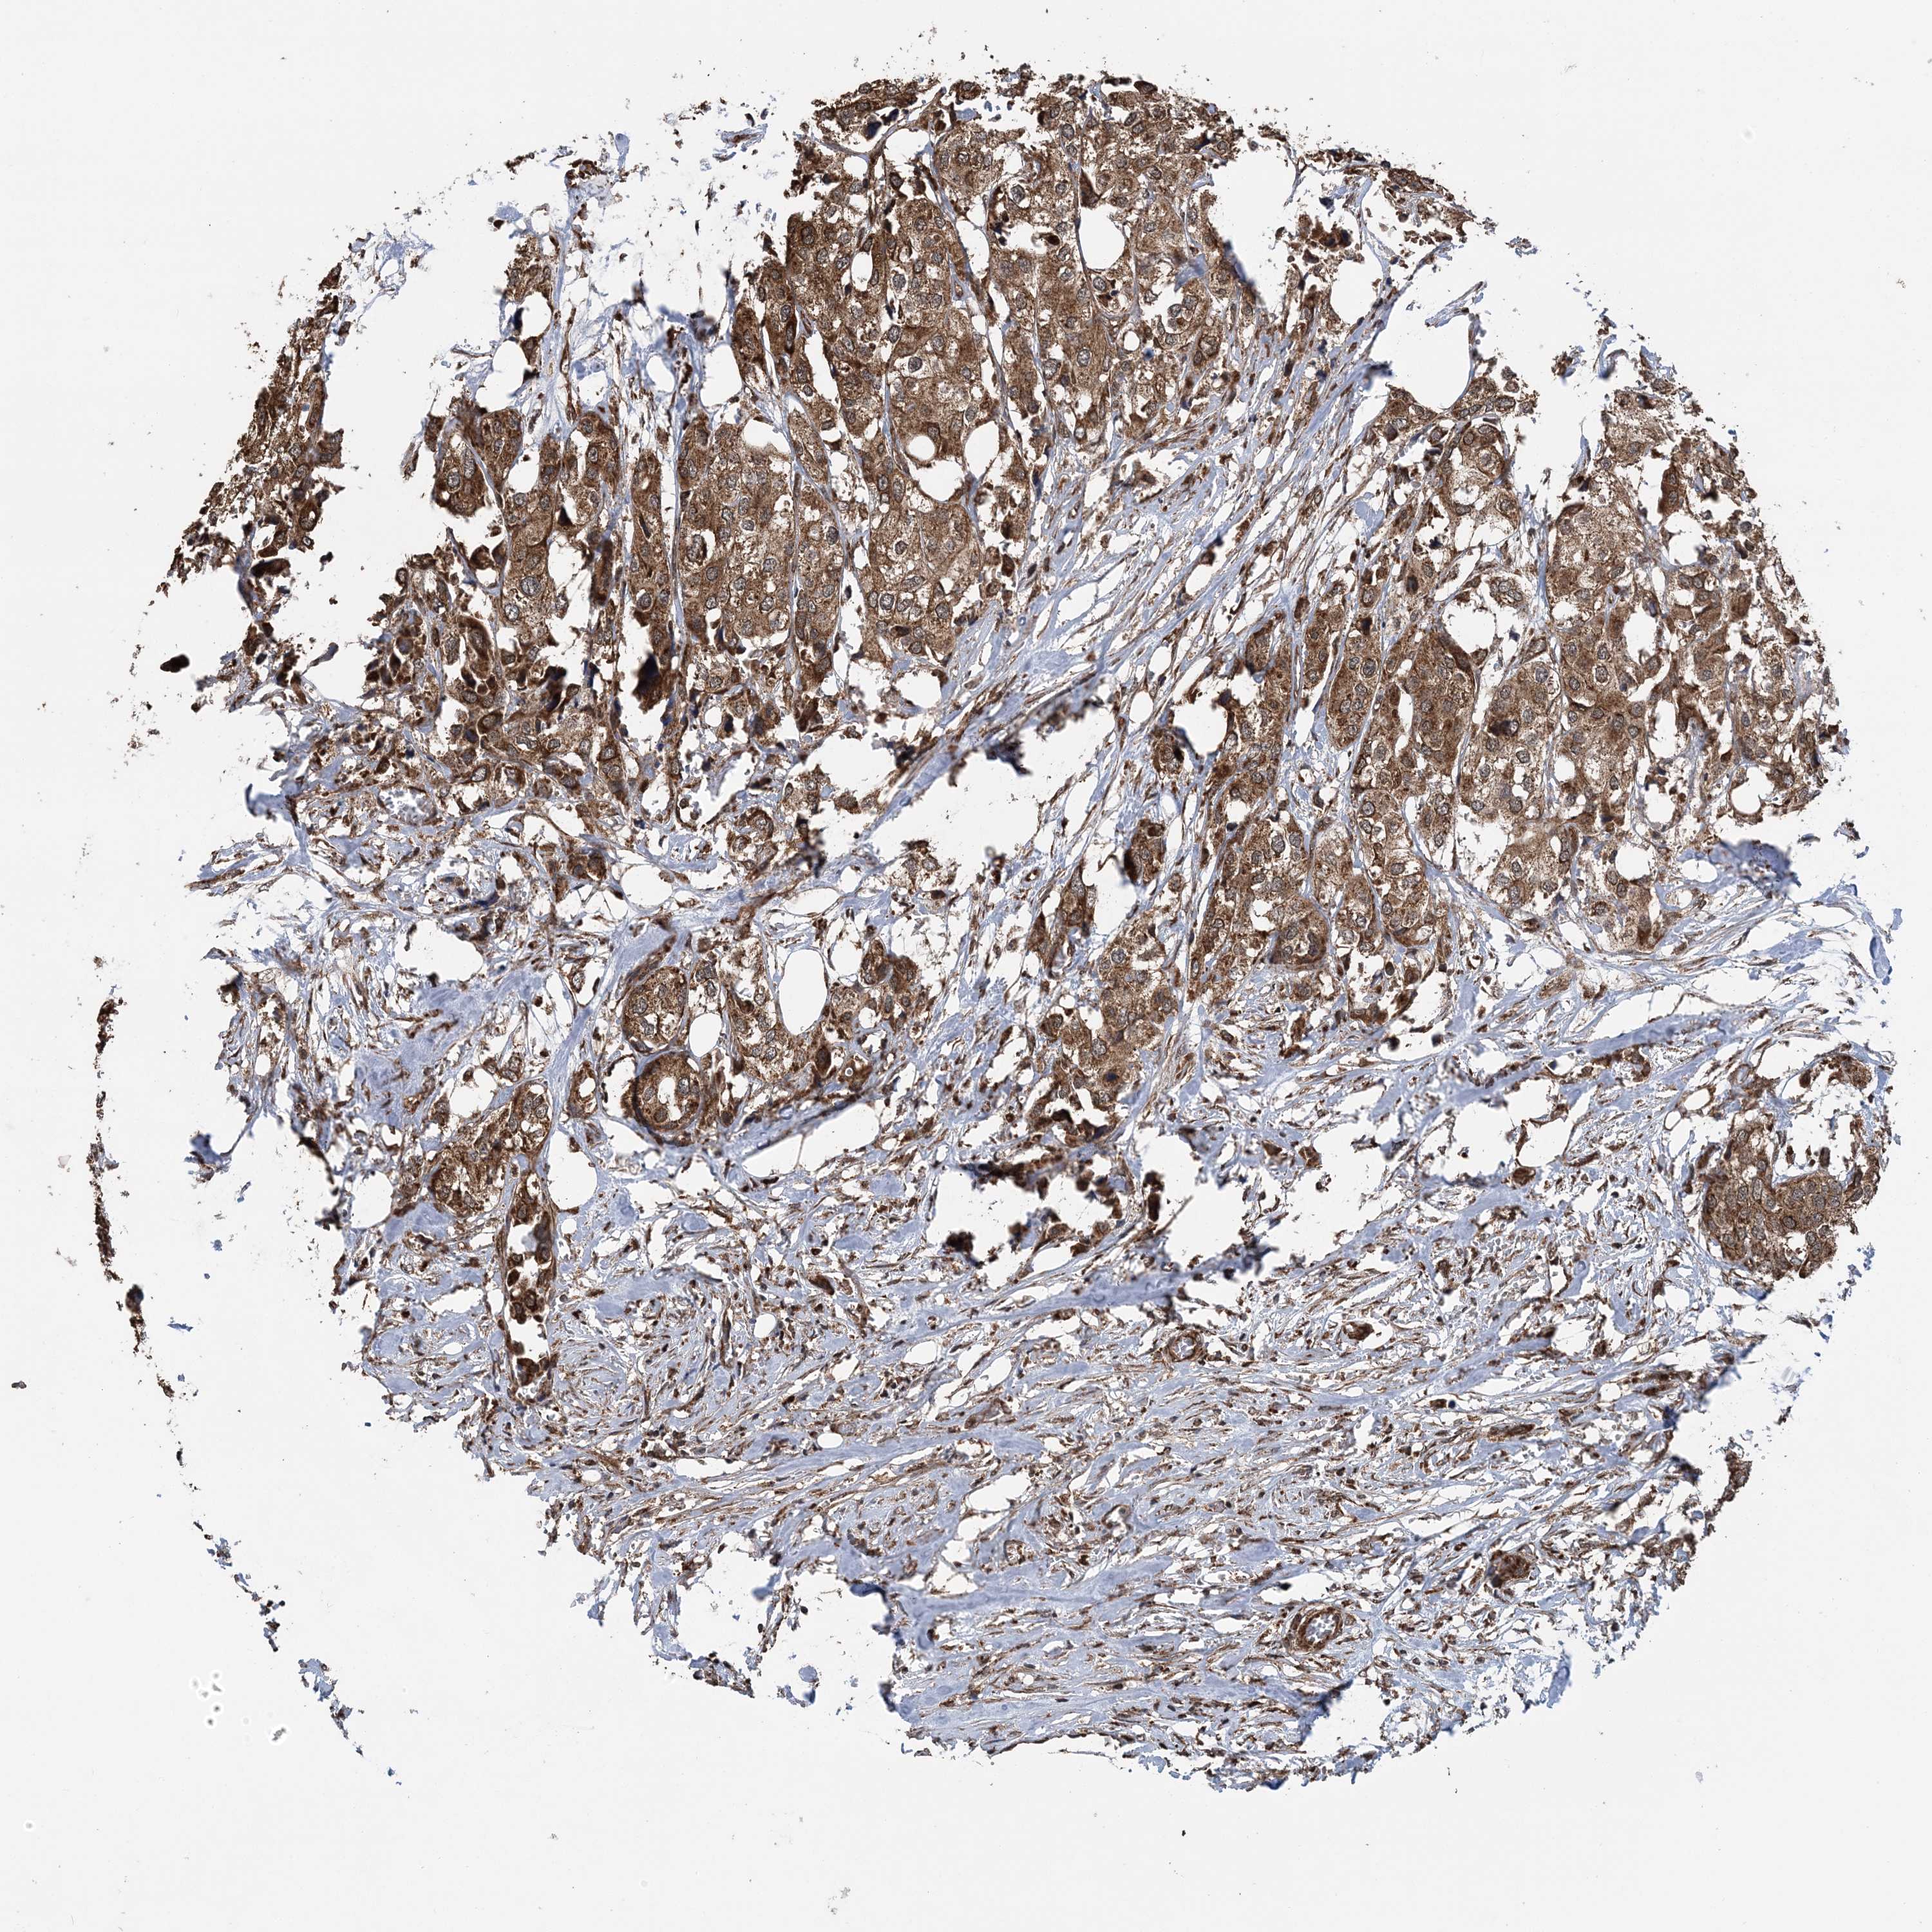

UROTHELIAL CANCER - Protein expressioni

A mouse-over function shows sample information and annotation data. Click on an image to view it in a full screen mode. Samples can be filtered based on level of antibody staining by selecting one or several of the following categories: high, medium, low and not detected. The assay and annotation is described here.

Note that samples used for immunohistochemistry by the Human Protein Atlas do not correspond to samples in the TCGA dataset.

Antibody stainingi

Antibody staining in the annotated cell types in the current human tissue is reported as not detected, low, medium, or high, based on conventional immunohistochemistry profiling in selected tissues. This score is based on the combination of the staining intensity and fraction of stained cells.

Each image is clickable and will lead to virtual microscopy that enables deeper exploration of all samples and also displays staining intensity scores, fraction scores and subcellular localization as well as patient and tissue information for each sample.

Antibody CAB037113

Staining

High

Medium

Low

Not detected

Intensity

Strong

Moderate

Weak

Negative

Quantity

>75%

75%-25%

<25%

None

Location

Nuclear

Cytoplasmic/membranous

Cytoplasmic/membranous,nuclear

Urothelial carcinoma, Low grade

Urothelial carcinoma, High grade